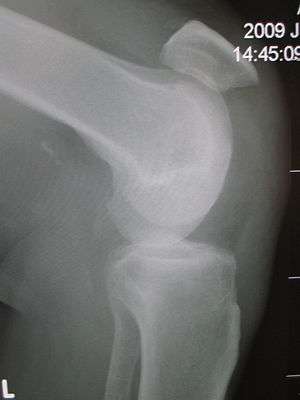

Patellar tendon rupture showing a marked distance between the tibial tuberosity and the bottom of the patella.

The tell-tale sign of a ruptured patella tendon is the movement of the patella further up the quadriceps. When rupture occurs, the patella loses support from the tibia and moves toward the hip when the quadriceps muscle contracts, hindering the leg's ability to extend. This means that those affected cannot stand, as their knee buckles and gives way when they attempt to do so.

Patellar tendon rupture can usually be diagnosed by physical examination. The most common signs are: tenderness, the tendon's loss of tone, loss of ability to raise the straight leg and observation of the high-riding patella. Radiographically, patella alta can be detected using the Insall and Salvati method when the patella is shorter than its tendon. Partial tears may be visualized using MRI scans.[1]